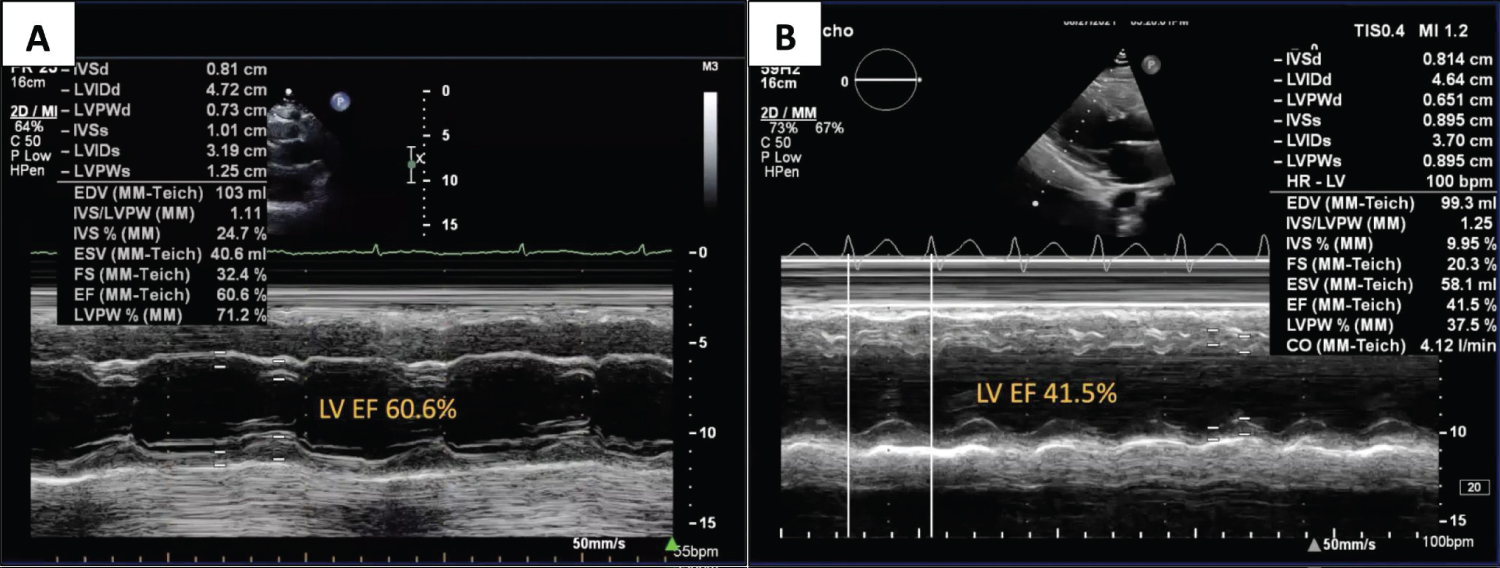

A 27-year-old female with Gitelman syndrome was initially admitted due to a three-day history of high grade fever, abdominal pain and loose stool. The patient was managed as a case of dengue fever with warning signs. She had positive dengue nonstructural protein 1 (NS1) antigen, thrombocytopenia of 29,000, severe transaminitis of 85x the upper limit of normal (ULN), increasing creatinine trends with glomerular filtration rate (GFR) of 19 and persistent multiple electrolyte imbalance showing hypokalemia, hypomagnesemia and hypocalcemia. Supportive management with hydration, continuous electrolyte correction, and antipyretics were given. The patient was clinically improving, however, during the convalescent phase of dengue; she developed recurrent loss of consciousness lasting for less than 30 seconds which was preceded by nausea, vomiting and palpitation. There were no seizure-like symptoms or any abnormal tone elicited. She had a history of febrile seizures during childhood. There was no history of epilepsy, transient loss of consciousness, or recent head trauma. She had no history of previous dengue infection. There was no history of sudden cardiac death, arrhythmia, or congenital disease among family members. She is a non-smoker, non-alcoholic beverage drinker, and has no history of illicit drug use. There was complete spontaneous recovery after regaining consciousness. She was awake, oriented to three spheres. She was hemodynamically stable with a blood pressure of 140/80, heart rate of 80 beats per minute (bpm), and respiratory rate of 22 cycles per minute (cpm). There was no desaturation, pallor or cyanosis. There was no carotid bruit. The jugular venous pressure was 8 mmHg above the sternal angle. On the cardiac examination, there were distinct S1 and S2 sounds, no heaves, lifts, thrills, murmur, or S3 gallop. Pulses were full and equal in all extremities with no bipedal edema. The ECG showed normal sinus rhythm with a corrected QT interval (using the Bazett formula) was 0.54 seconds (Figure 1A), hence was monitored closely. On the next hospital day, there was recurrence of syncope and ECG showed an "R-on-T" phenomenon initiated by a "short-long-short" sequence as represented by a premature ventricular complex (PVC) with a long compensatory pause followed by a sinus beat with prolonged QT interval which was subsequently followed by a closely coupled PVC which triggered the TdP (Figure 1B). She was given magnesium sulfate intravenously, eventually converting the rhythm to sinus. Other cardiac workups showed evidence of cardiac injury with high sensitivity Troponin I (HsTropI) of 18.20. Transthoracic echocardiogram (TTE) showed decreased systolic function with an ejection fraction (EF) of 41.9% from 61.6% with grade II left ventricular diastolic dysfunction (Figure 2). There was new wall motion abnormality described as left ventricular global hypokinesia with the best contraction in the apical inferior interventricular septum and basal inferolateral segment. The cranial CT scan showed normal results. She had decreasing trends of creatinine and transaminases, but there were persistent hypokalemia (2.7 mEq/L) and hypomagnesemia (1.3 mEq/L) and elevated inflammatory markers. Arterial blood gas showed normal acid base balance with adequate oxygenation, and thyroid function tests, complete blood count (CBC) and coagulation studies were normal. She was transferred to the critical care unit wherein she presented with chest tightness. There was frequent non-sustained ventricular tachycardia (NSVT) and recurrence of loss of consciousness, there was no pulse or blood pressure appreciated. Hence code blue was activated and ACLS was initiated. She was subsequently intubated with return of spontaneous circulation (ROSC) after 6 minutes of resuscitation. However, there was a recurrence of pulselessness and ECG showed pulseless VT. Defibrillation using a biphasic shock of 200J was done with conversion to sinus rhythm and ROSC. A 24 hour holter was requested and showed frequent non-sustained ventricular tachycardia with longest beat of 13 seconds and episodes of torsades de pointes (Figure 3). To prevent recurrence of cardiac dysrhythmia, a temporary transvenous pacemaker was inserted to promote overdrive pacing, with a back up rate set to 100 bpm preventing “R-on-T” phenomenon (Figure 4). Eventually started on propranolol, a non selective blocker to reduce risk of recurrent arrhythmia. According to the latest ESC guidelines for the management of patients with ventricular arrhythmia and prevention of sudden cardiac death, there is Class I recommendation in giving non-selective beta-blockers (nadolol or propranolol) in long QT syndrome (LQTS) patients with documented QT interval prolongation to reduce risk of arrhythmic events and initiating transvenous pacing to increase heart rate in patients with recurrent torsades de pointes [8]. Decision to insert implantable cardioverter defibrillator (ICD) was still controversial since recommendations to insert ICD are indicated in patients with syncope with depressed cardiac function, and ventricular tachycardia without correctable cause [9]. In the patient’s case, syncope was attributed to dengue myocarditis aggravated by electrolyte wasting secondary to Gitelman syndrome. Hence, regular electrolyte monitoring and aggressive correction was maximized to prevent further risk of cardiac dysrhythmia.

Figure 2: Transthoracic echocardiogram.

TTE in M-mode showing remarkable reduction in EF from 60.6% to 41.5% by Teichholz method. View Figure 2